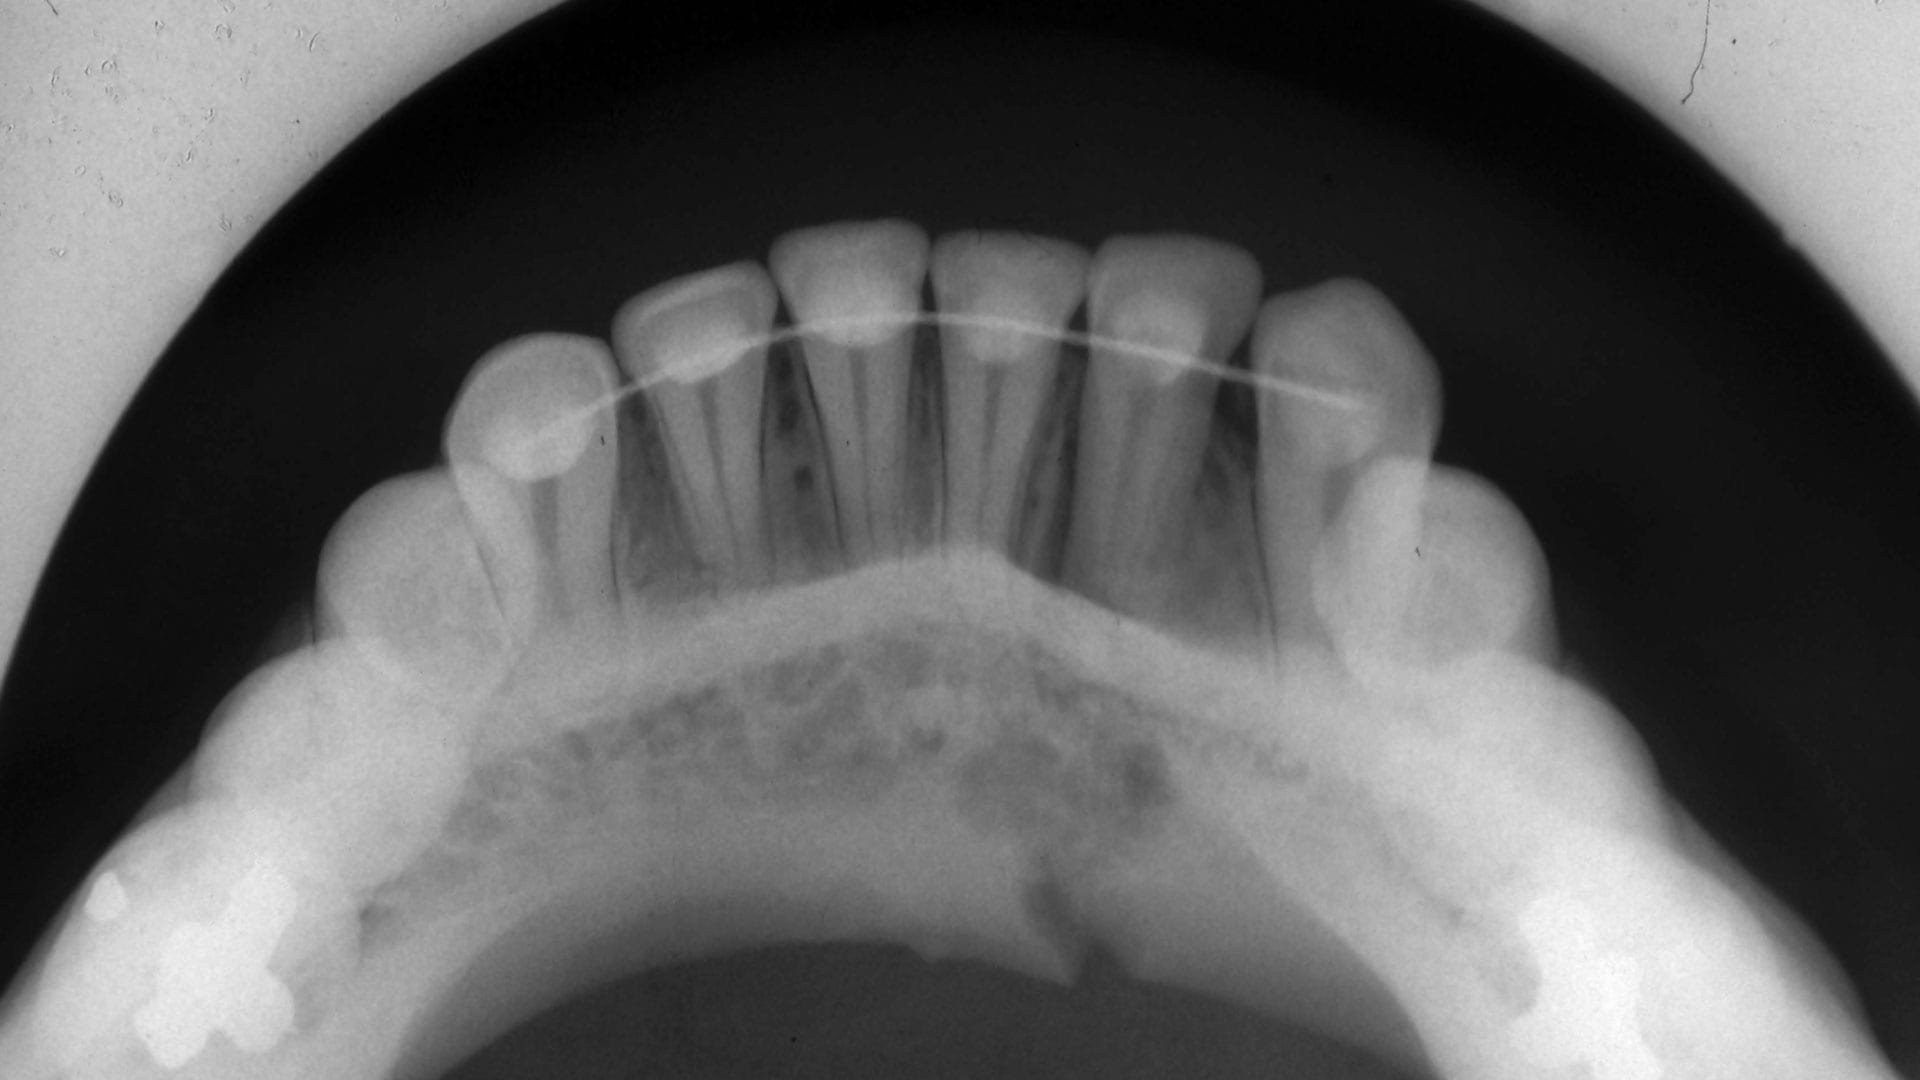

occlusal X Ray

Occlusal

This is done when your jaw is closed, to see how your upper and bottom teeth line up. It can also be used to detect anatomical abnormalities with the floor of the mouth or palate.